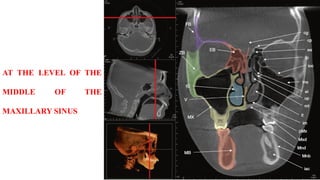

AT THE MID MAXILLARY

SINUS LEVEL

AT THE LEVEL OF THE

MIDDLE OF THE

MAXILLARY SINUS

AT THE MIDMAXILLARY SINUS LEVEL

AT THE LEVELOF THE MIDDLE OF THE MAXILLARY SINUS